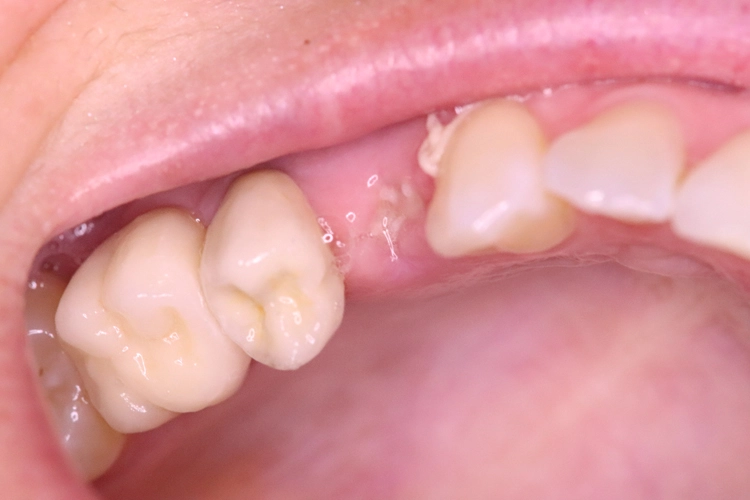

Die 43-jährige Patientin stellte sich mit einem schmerzenden, perkussionsempfindlichen Zahn 14 vor, der vor ca. 15 Jahren endodontisch behandelt wurde. Die Patientin nimmt seit Jahren Medikamente ein, die die Blutgerinnung beeinflussen. Sie hat eine gute Mundhygiene und ist Nichtraucherin.

Nach Aufklärung über die möglichen Therapien (Revision, WSR) entschied sich die Patientin für eine Extraktion und Implantatversorgung mit einem Keramikimplantat. Die Nachbarzähne 15, 16 waren bereits durch Implantate ersetzt und eine Brücke kam für sie nicht in Frage.

Nach der ersten klinischen Befundaufnahme und Fotodokumentation der Ausgangssituation (Abb. 1) wurde zur Ergänzung des klinischen Befundes eine Einzelzahnaufnahme erstellt (Abb. 2). Vom Oberkiefer wurde eine Abformung genommen, um eine Tiefziehschiene herzustellen. Diese wird direkt am OP-Tag genutzt, um eine provisorische Krone herzustellen.